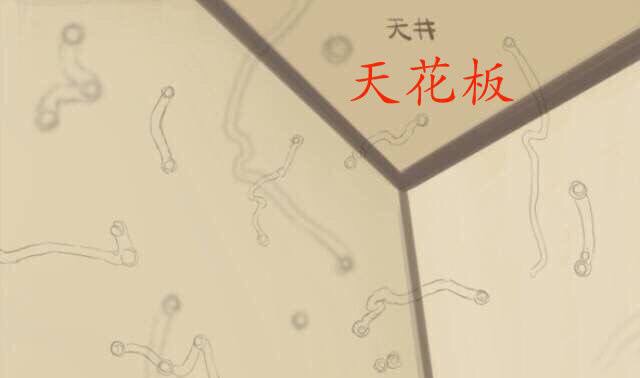

A:飛蚊症是指眼前有飄動的黑影,尤其是看白色背景的時候症狀更加明顯,同時有時候有些人會伴有閃光感,眼前一亮一亮的症狀,引起的原因主要是玻璃體液化和後脫離。絕大多數的飛蚊症都是生理性,但是有大約20%的飛蚊症,可能是病理性,具有威脅視力下降的情……

A:眼睛出現飛蚊,可以通過以下方法進行治療並緩解:1、藥物治療:藥物治療飛蚊療效並不確切,眼睛出現飛蚊又稱玻璃體混濁,可以分為生理性的玻璃體混濁和病理性的玻璃體混濁。生理性的飛蚊症,主要是由於隨著年齡的增加,玻璃體逐漸液化所導致,通常對患者的……

A:眼睛裡有飛蚊的現象主要是因為玻璃體發生了液化、變性和混濁,玻璃體原本在眼睛裡邊是一個膠凍狀的結構,由於近視眼以及中高度近視或者年齡過大了,中老年人就會出現玻璃體的液化、變性和混濁,這種情況下很難通過任何治療,將已經液化的玻璃體恢復到膠凍狀的……